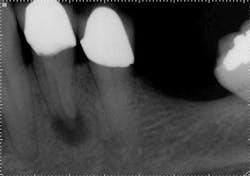

Mandibular premolars

Mandibular premolars can be very difficult to treat and are associated with a high rate of post-treatment disease that is most likely due to anatomic variability. (11) This anatomical variability in mandibular premolars is similar to that of maxillary premolars and is a possible reason why root canal treatment may fail in premolar teeth in general. Similar to maxillary premolars, the clinical crowns taper to a thin root at the CEJ, resulting in very little or no margin for error when accessing the pulp chamber. It is not uncommon to have more than one canal in these teeth. Several studies indicate a second canal is present in more than 25% of mandibular first premolars. (12,15)Often when two canals are present, the second canal is displaced to the lingual and can be very difficult to locate. (Figure 5) Many mandibular first premolars have significant lingual inclination of the root, making the second canal almost impossible to locate because the lingual canal often branches off the main canal at or near a 90-degreeangle. If a single canal is present, it tends to be broad in the buccal-lingual direction, and this makes it difficult to remove biofilm from all root surfaces. Mandibular second premolars also have a high degree of anatomic variability, but not to the same degree as mandibular first premolars. The reported incidence of multiple canals in mandibular second premolars ranges from 1.2% to 29%. (12,18)As with first premolars, many mandibular second premolars have some lingual inclination of the root and a broad buccal-lingual canal dimension results in difficulty contacting all surfaces of the canal with any instrumentation technique.

with conventional radiography, and this branching could be better

visualized with CBCT.